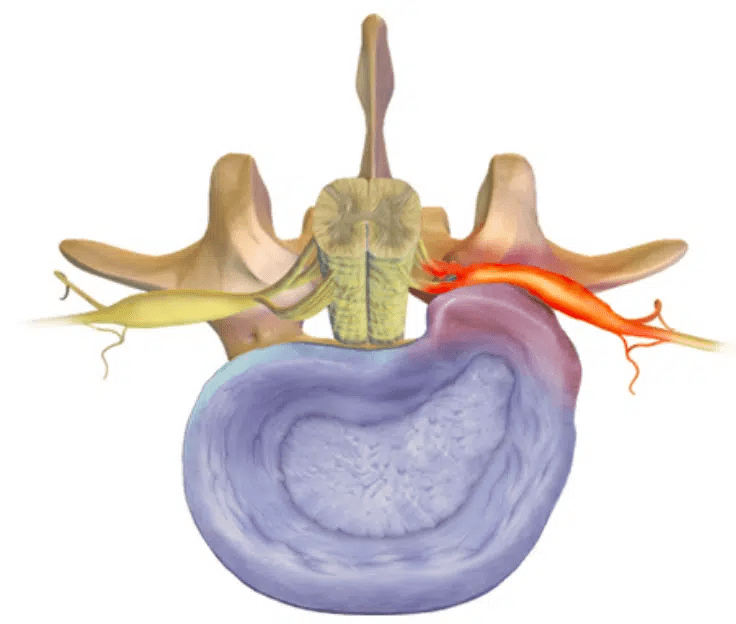

• Lumbal skiveprolaps – Del 1: Hva er prolaps?

Lumbal skiveprolaps – Del 1: Hva er prolaps?